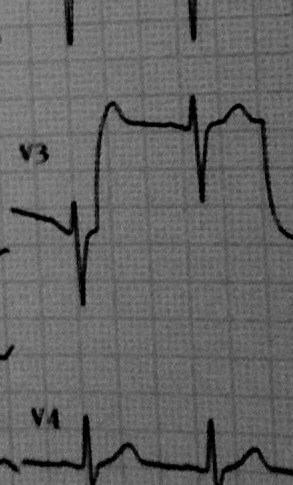

This head doctor had nothing better to offer, than to prescribe 4 types of dahls.

My analyst, um… ok psychiatrist, says I have a lot of anger inside of me. The true genius that he is.

Anger or not, I require a fork, fucktard.